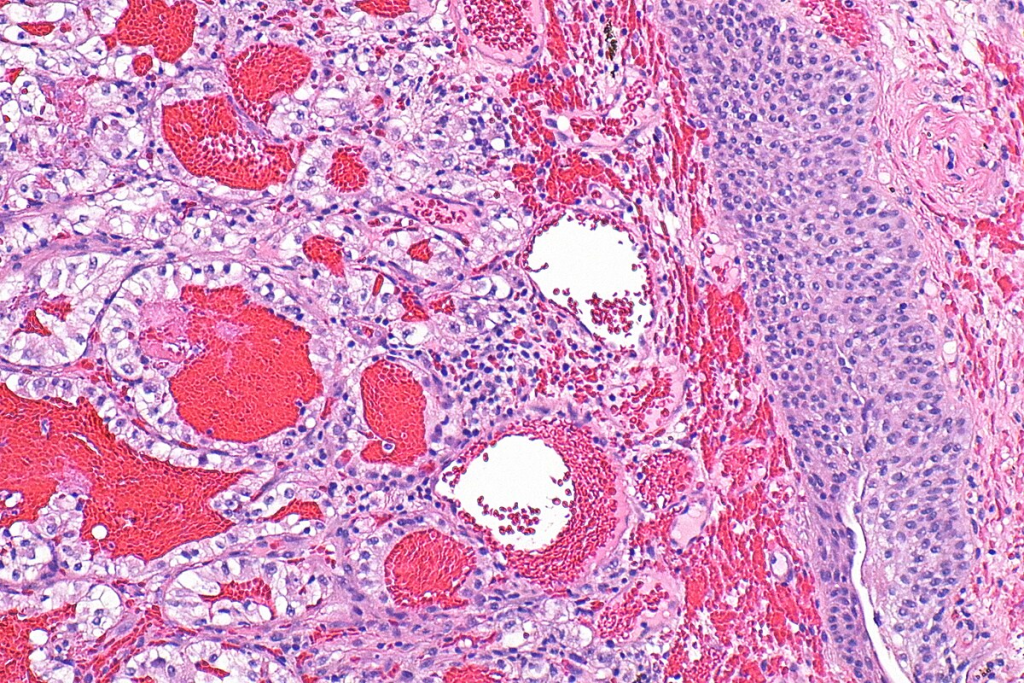

There are several types of bladder cancer, with urothelial carcinoma being the most common, making up about 90% of cases. Other types include squamous cell carcinoma and adenocarcinoma. Bladder cancer is more common in men than women. It’s among the top ten most common cancers worldwide.

The mpMRI for bladder cancer includes T2-weighted images, diffusion-weighted imaging (DWI), and dynamic contrast-enhanced (DCE) sequences. T2-weighted images show the bladder’s anatomy. DWI spots tumors and checks their aggressiveness. DCE sequences look at blood flow in bladder lesions.

Together, these parts give a full view of the tumor. T2 images check how deep the tumor is. DWI and DCE show how aggressive the tumor is and how it might react to treatment.